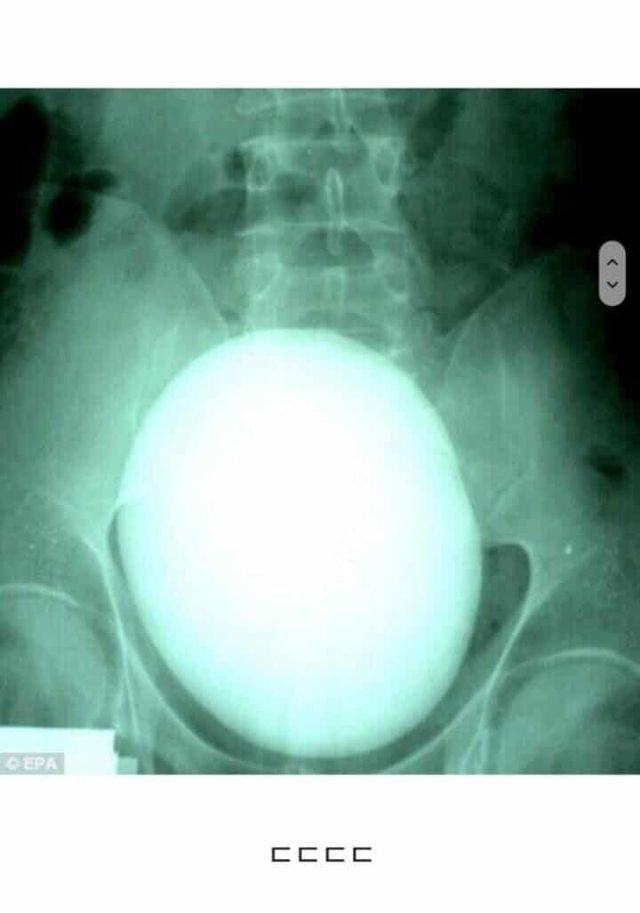

이게 당신의 요로결석입니다